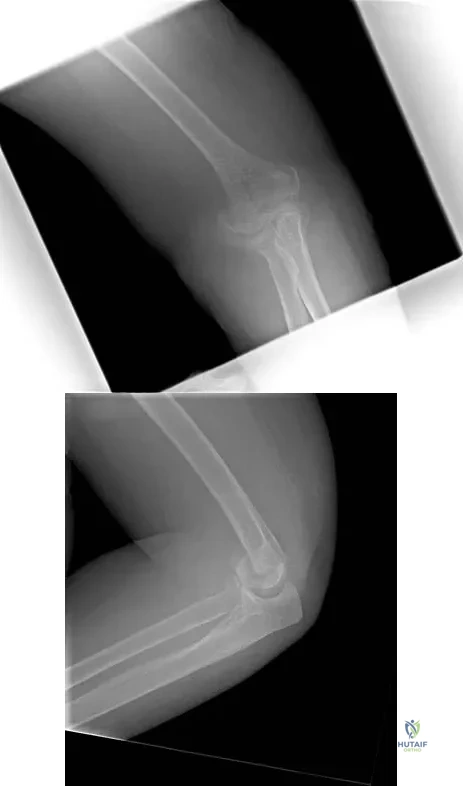

Question 81

A right-handed 14-year-old pitcher has had a 3-month history of shoulder pain while pitching. Examination reveals full range of motion, a mildly positive impingement sign, pain with rotational movement, and no instability. Plain AP radiographs of both shoulders are shown in Figures 25a and 25b. Management should consist of

Explanation